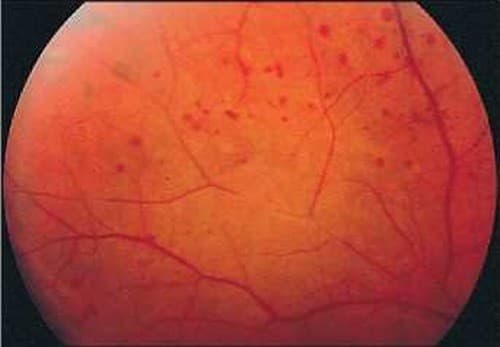

4.Huyết áp quá cao

Ngoài tăng nguy cơ bệnh tim và đột qụy, huyết áp cao không được điều trị cũng có thể phá hỏng các mạch máu ở võng mạc, gọi là bệnh võng mạc tăng huyết áp.